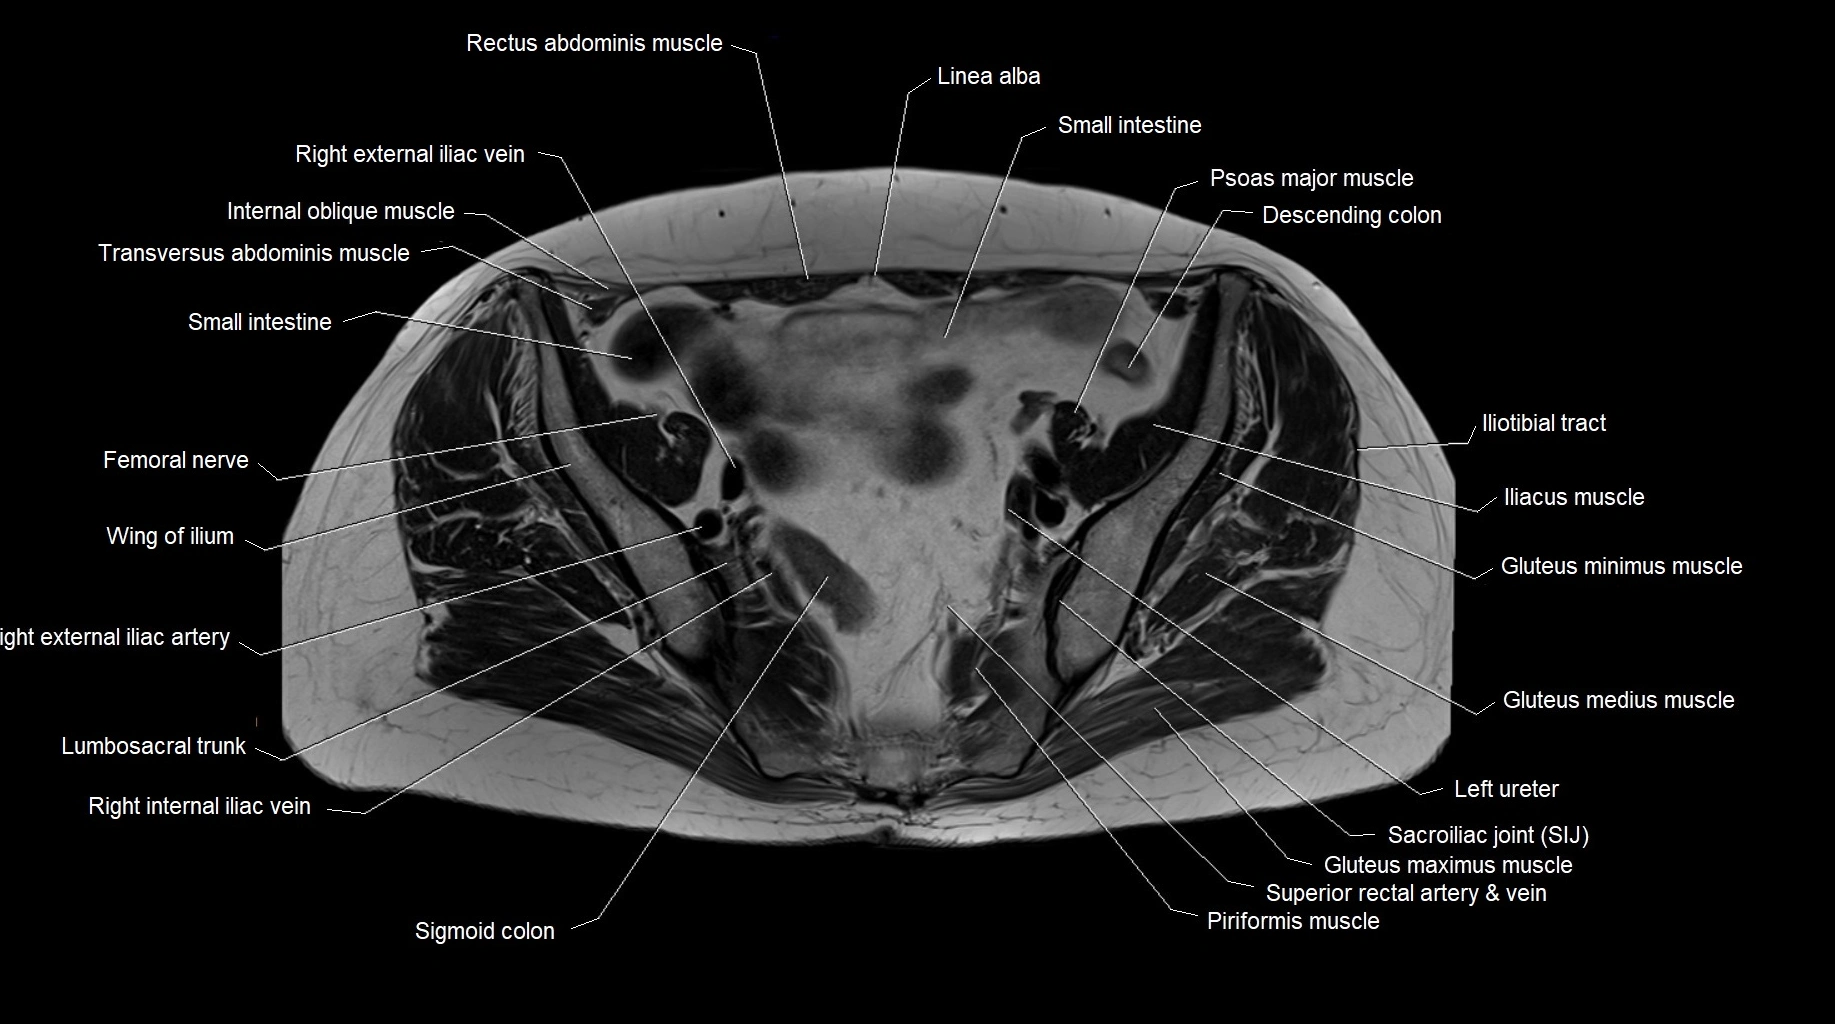

MRI images